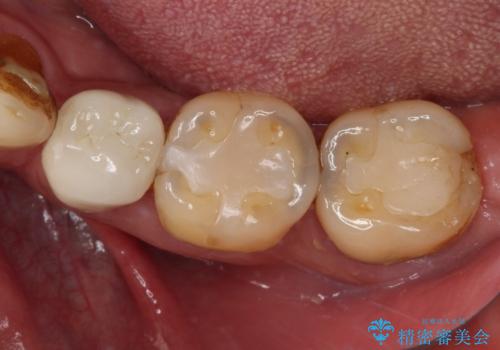

- 奥歯がしみるとのことで来院された患者様です。

診査をしたところ、目視でも明らかな、とても大きなむし歯があありました。

既に治療により詰め物が装着されている歯であったため、オールセラミッククラウンによる補綴治療を選択することとしました。